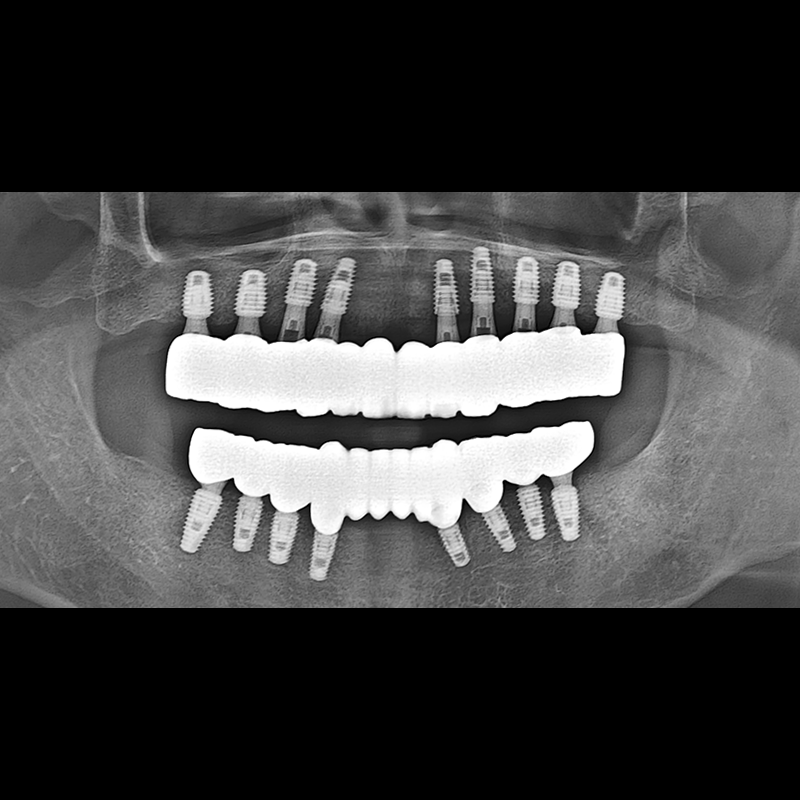

IMPLANT

BEFORE AFTER